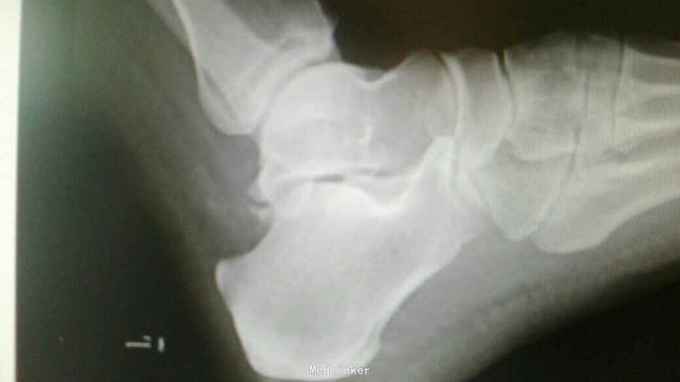

查体:左足跟部肿胀,外翻畸形,压痛,叩痛,活动受限。 X线:左侧距下关节外侧脱位。

诊断:左距下关节脱位 治疗:手法闭合复位。

随访:三个月无疼痛及活动受限。继续定期复查注意距骨坏死。 讨论:闭合性距下关节脱位,单纯跟距关节脱位可误诊。由于韧带卡压,使得手法复位难度加大,需要开放手术复位。如果手法得当多可复位成功,可免除手术。